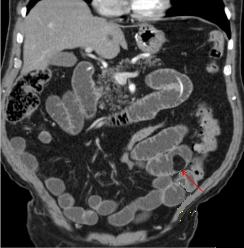

Lipome de

intestin a distance . Image ovoide hypo-dense a bord

lisse et net au region fosse iliaque gauche . Image

TDM en coupe coronal ( frontale ) |